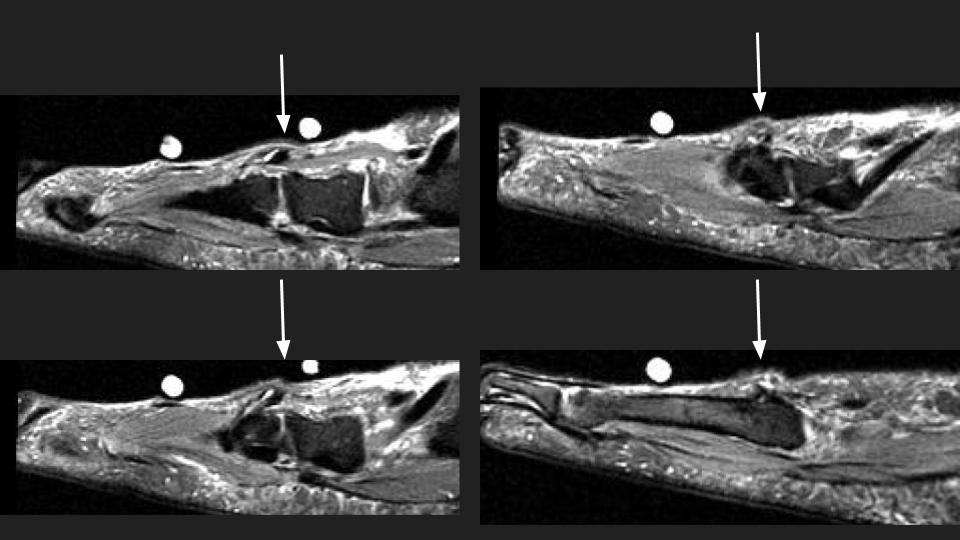

Area of pain indicated by markers surrounds the insertion of the Peroneus Tertius tendon onto the base of the 5th and likely also 4th dorsal MT base. The tendon is thickened with intrasubstance intermediate T1 and bright T1 signal. This is the insertional tendinosis of the peroneus tertius, with probable superimposed partial intrasubstance insertional tear suggested in the Sag fat sat images. The reference does not say much about the insertion, but includes some anatomic references that indicate variation in the insertion site at the 5th and sometimes 4th and 5th MT base. Reference article.